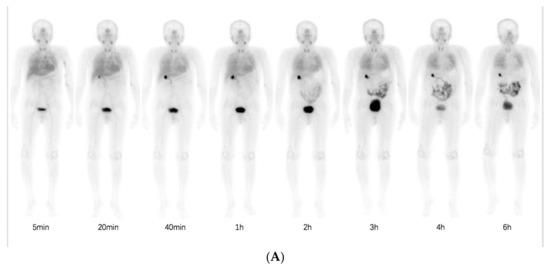

Normal physiological uptake of 99mTc-HFAPI was observed mainly in the liver, intestinal tract, pancreas, gallbladder, and to a lesser extent in the spleen, kidneys, and thyroid, with rapid clearance and no apparent retention in the blood circulation at the late time point, which was the same as in Jia et al.’s work [23]. Excessive uptake was seen in the lung area in the ILD patients at the early time points and was still visible even at 6 h after injection. A representative example of 99mTc-HFAPI distribution from whole-body scintigraphy in one of the ILD patients is shown in Figure 3. In addition, one ovarian cancer patient without affected lungs was purposely enrolled to evaluate the 99mTc-HFAPI distribution in the normal lung region. No abnormal uptake was observed in the healthy lung region (Figure S2).

Figure 3. Representative whole-body anterior projection images of a 59-year-old male patient at different time points (5 min, 20 min, 40 min, 1 h, 2 h, 3 h, 4 h, and 6 h) after intravenous injection of 99mTc-HFAPI (A). The semi-quantification of signal intensity ratios over time using whole-body planar images. The signal intensity ratios are the ratios of geometric mean counts of lung to whole body from anterior and posterior counts (B).